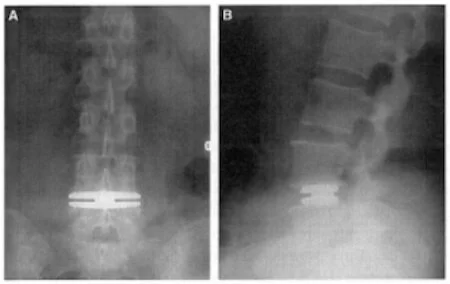

spine disc replacement .jpg

replacing artificial disk.jpg

xray disc replacement.jpg